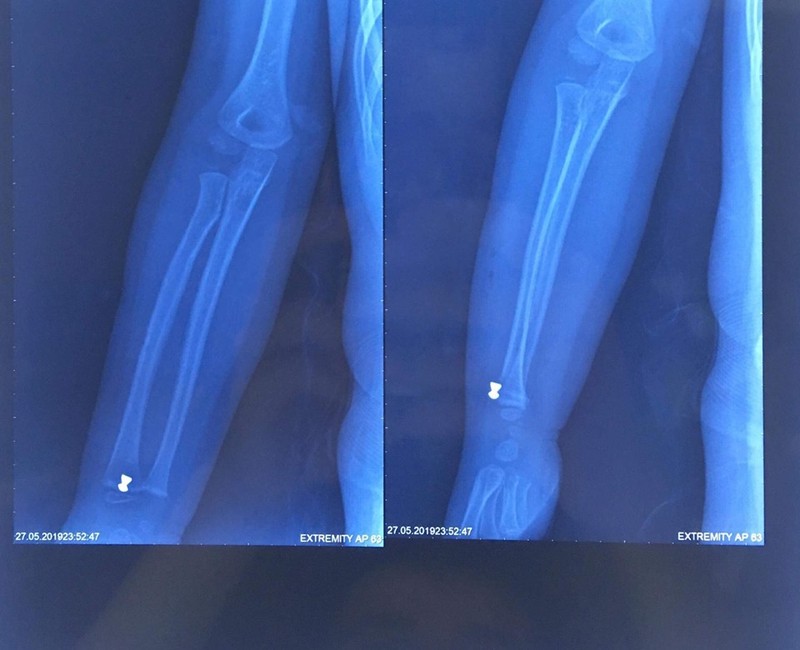

Trước đó, ngày 27/5, bé N.H.K, 5 tuổi ở Sóc Sơn, Hà Nội, được chuyển đến cấp cứu tại Bệnh viện Xanh Pôn trong tình trạng cẳng tay phải bị thương do hỏa khí. Gia đình bé cho biết, trong khi chơi trốn tìm cùng bạn, bé vô tình bị trúng đạn súng hơi do người dân bắn chuột. Gia đình đã đưa bé đến cấp cứu tại Bệnh viện Đa Khoa Sóc Sơn và sau đó là Bệnh viện Xanh Pôn. Tại đây, các bác sĩ đã khám và làm các chỉ định cận lâm sàng cho bé. Kết quả chụp XQ cho thấy, cẳng tay phải của cháu bị găm dị vật 0.5 cm, nên ngay lập tức, bé được chỉ định mổ cấp cứu để lấy dị vật.

Trao đổi với PV VietTimes, BS. Phạm Xuân Hưng cho hay, bé nhập viện trong tình trạng dị vật găm gần sát xương, các bác sĩ đã phải dùng máy X – Quang C – arm để xác định vị trí trực tiếp của dị vật. Sau nửa tiếng phẫu thuật, dị vật ở cẳng tay phải đã được lấy ra.